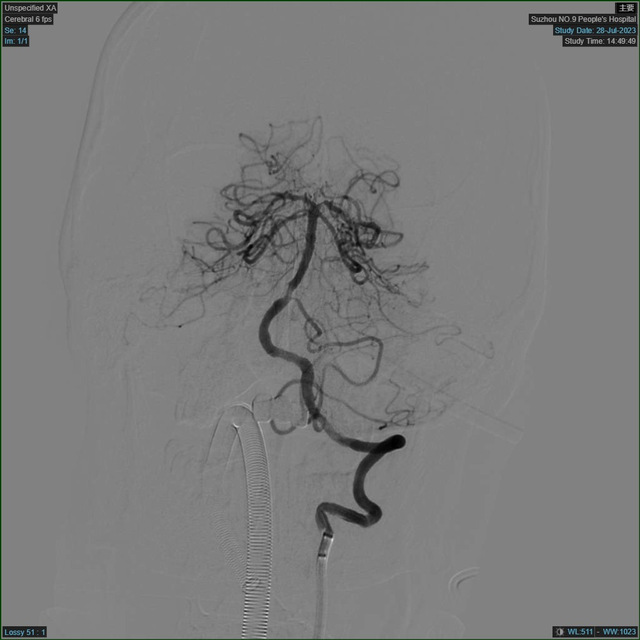

患者在医学影像科完成血管评估后,再次予以查体,评估神经功能缺损评分高达29分。神经内科副主任翟国杰阅片后考虑基底动脉闭塞,立即向家属交代相关情况,排除手术禁忌,签署手术知情同意书,完善所有术前检查,送至介入手术室,急诊介入手术立即进行。

DSA手术室

患者的血管情况远比预计的复杂,维持生命意识的最主要的血管——基底动脉主干发生了闭塞,这样的病变可引起肢体瘫痪、昏迷、甚至死亡。这种手术病变复杂,手术时间长,再通率低,对医生的体力和技术经验都是极大的挑战。医护团队密切协作配合,手术有条不紊地进行,迅速实施脑动脉取栓术。经过2小时的抢救,患者堵塞的血管终于被成功打通,左侧肢体活动明显增多,而此时没有人注意到,手术医师20多斤的铅衣压在身上长达几小时,已经全身湿透。